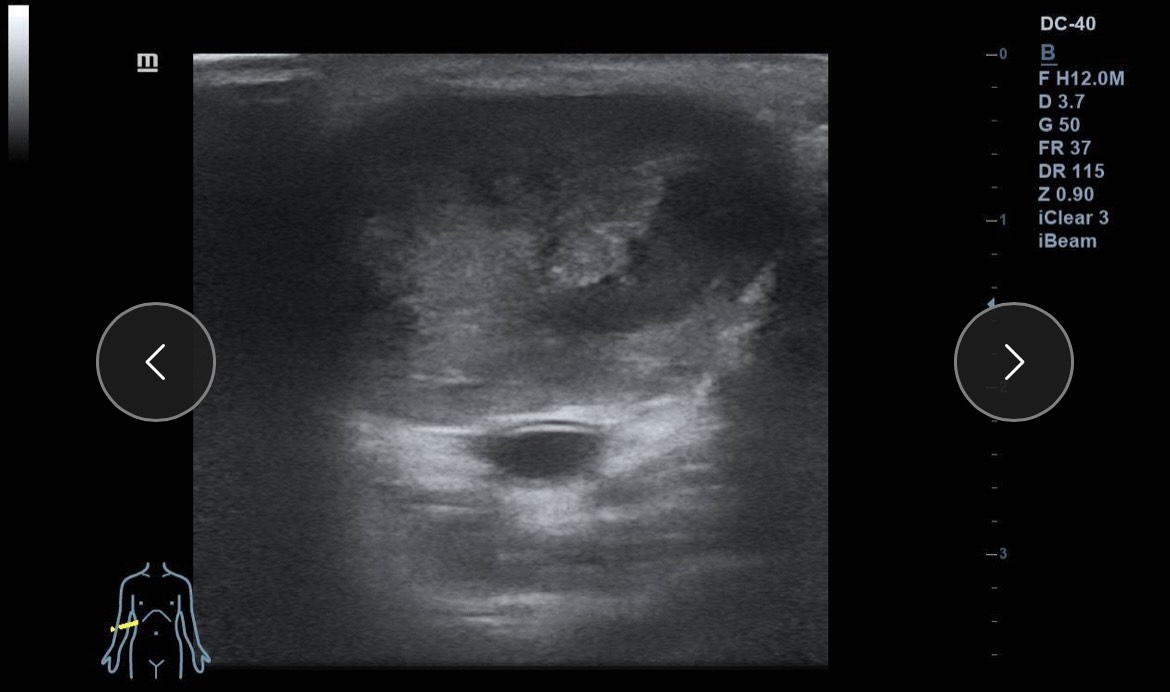

Ante la sospecha de patología vascular, se realiza ecografía clínica en la consulta.

Hallazgos ecográficos

Ecografía Doppler: dilatación aneurismática sacular de la arteria braquial (3 cm), bien delimitada, con trombo mural no oclusivo y flujo turbulento. Flujo arterial proximal y distal conservado. Sin signos de rotura ni hematoma adyacente.